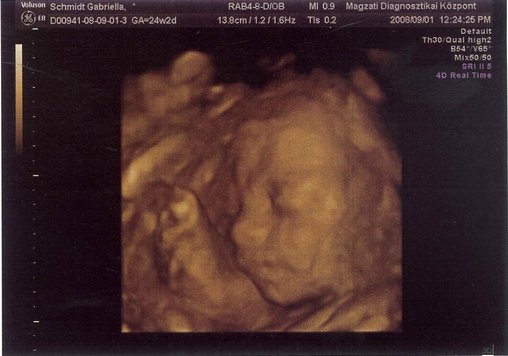

cili. szep a pocid.